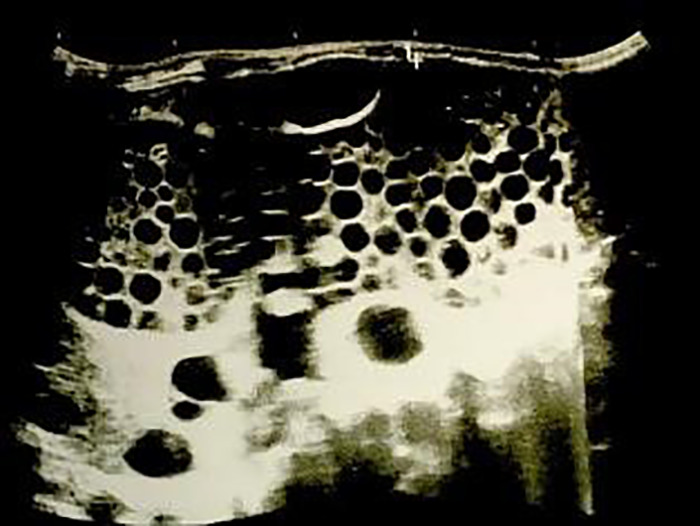

如果不及时诊断和治疗,包虫病破裂可导致腹内囊性包虫病的播散性发展。过敏性休克是囊肿破裂的明确指征。该临床病例为一名患有播散性囊性包虫病的年轻运动员,于2023年在哈萨克斯坦Syzganov国家外科科学中心进行了调查。该疾病在运动训练期间腹部运动损伤后逐渐发展,并伴有过敏性休克的模糊迹象。在接下来的2年里,腹腔棘球蚴病无症状。囊性包虫病的临床表现是在过去10-12周内逐渐发展起来的,表现为沉闷、腹痛、乏力、出汗、恶心、食欲不振、体重减轻。该病的亚急性表现与急性阑尾炎相似。诊断性剖腹检查显示腹腔内有大量囊性形成,需要鉴别诊断是否为弥散性腹结核伴肠系膜淋巴结损害。然而,对寄生虫的仪器验证,加上肺外结核的形态学排除,使得有可能建立一种播散性囊性包虫病。患者接受了膀胱切除术,出院时情况良好,并被告知疾病复发的可能性。总之,在高流行区,建议对所有腹部运动损伤进行棘球蚴病免疫检测,而不考虑是否存在过敏性休克症状。

Rupture of a hydatid cyst can lead to the development of a disseminated form of intra-abdominal cystic echinococcosis if not diagnosed and treated promptly. Anaphylactic shock is a definite indication of cyst rupture. The presented clinical case was a young athlete with a disseminated form of cystic echinococcosis, which was investigated in 2023 at the Syzganov National Scientific Center for Surgery of Kazakhstan. The disease developed gradually following a sports injury to the abdomen during sports training and was accompanied by blurred signs of anaphylactic shock. In the next 2 years, echinococcosis of the abdominal cavity was asymptomatic. The clinical manifestation of cystic echinococcosis developed gradually over the last 10-12 weeks, in the form of dull, painful abdominal pain, malaise, weakness, sweating, nausea, poor appetite, and weight loss. Subacute manifestations of the disease resembled those of acute appendicitis. A diagnostic laparotomy revealed an abundance of cystic formations in the abdominal cavity, necessitating a differential diagnosis between a disseminated form of abdominal tuberculosis with damage to the mesenteric lymph nodes. However, instrumental verification of the parasite, together with the morphological exclusion of the extrapulmonary form of tuberculosis, made it possible to establish a disseminated form of cystic echinococcosis. The patient underwent a cystectomy, was discharged in satisfactory condition, and was informed about the possibility of disease recurrence. In conclusion, in hyperendemic zones, it is recommended to carry out immunological testing for echinococcosis on all abdominal sports injuries, independent of the presence of anaphylactic shock symptoms.